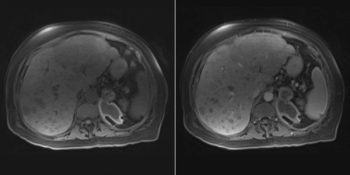

A 63-year-old man with NET metastatic to the liver undergoes MRI for evaluation of response to therapy. Based on the imaging, what is your diagnosis?